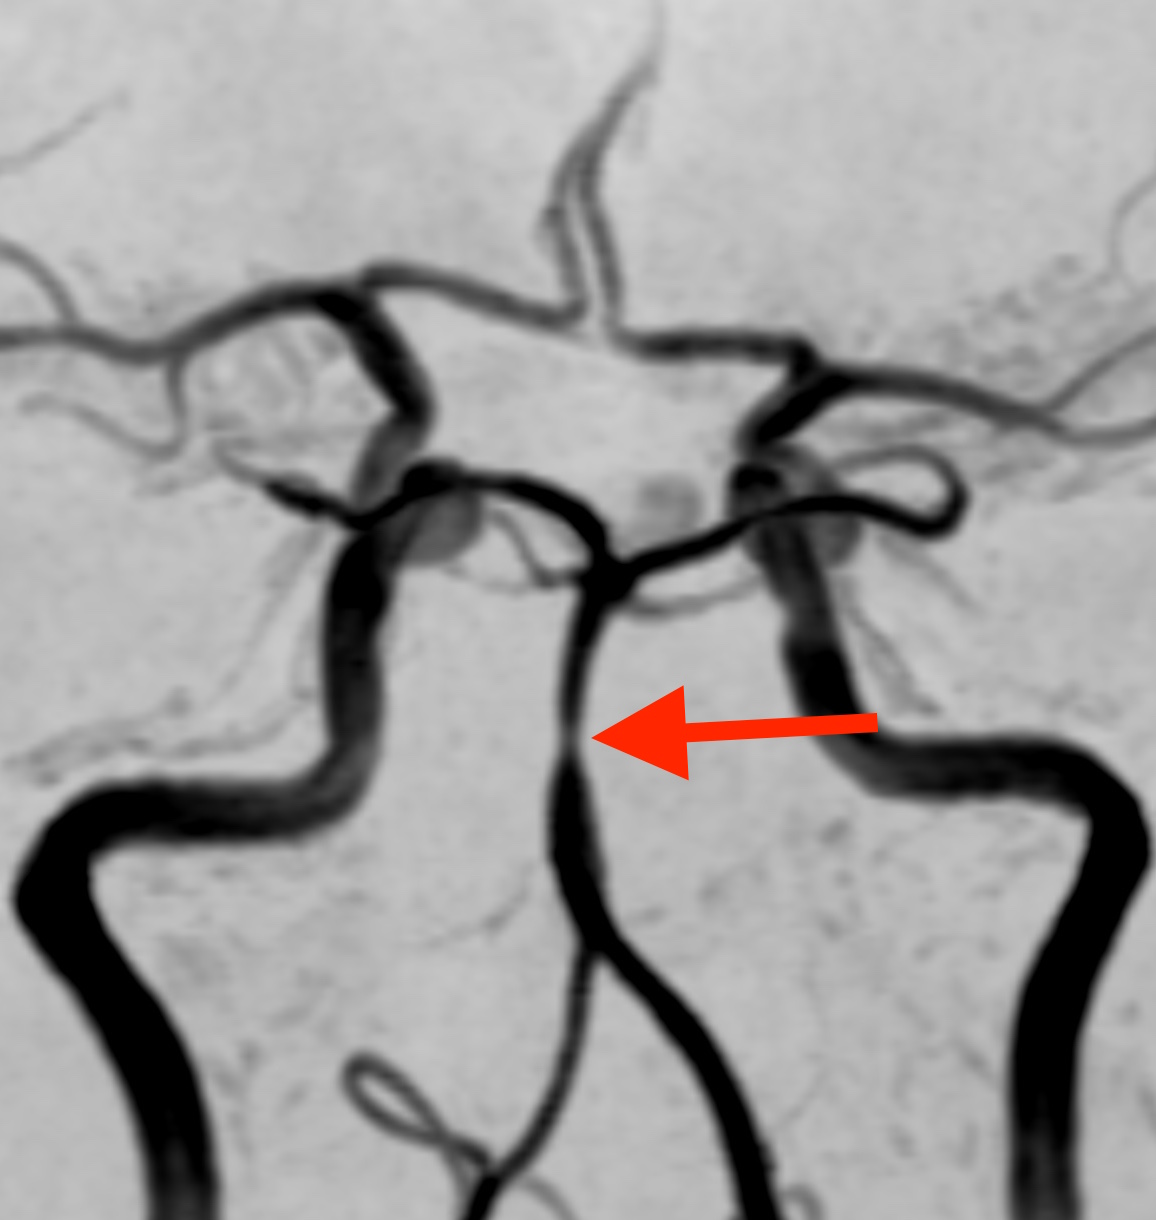

MRI検査で脳の血管を見たところ、

脳底動脈という血管の一部がくびれて細くなっており、その下の部分では、血管がソーセージのような形に膨らんでいます。この所見から可逆性脳血管攣縮症候群(RCVS)と診断しました。